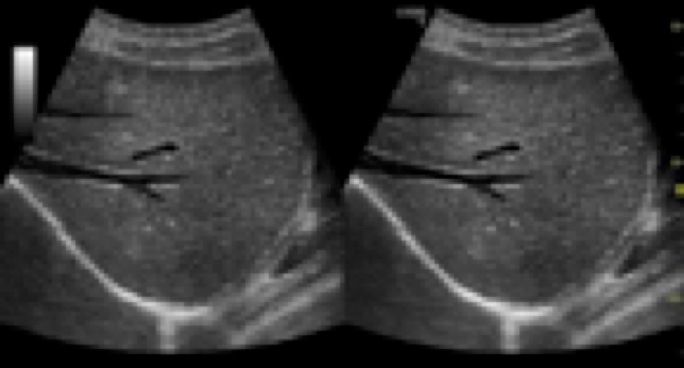

- B-Steer Plus con reconocimiento de la aguja.

– NEDDLE RECOGNITION

Software de ayuda para la punción.